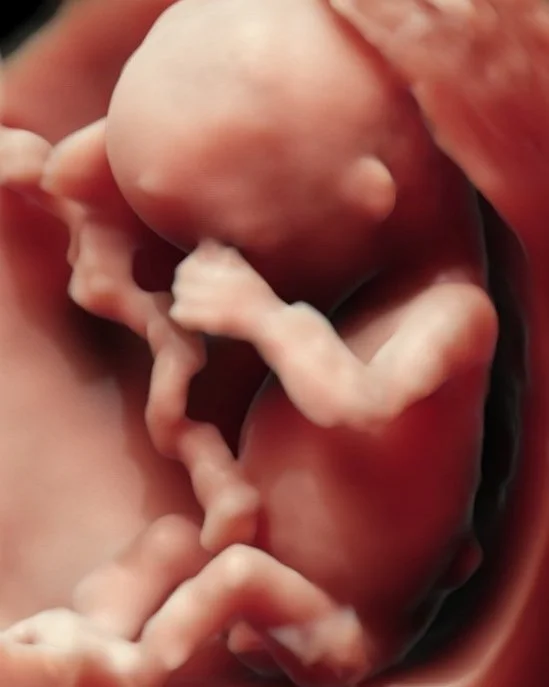

El ultrasonido 4D va un paso más allá y nos permite ver al bebé en movimiento. Es como una pequeña película donde podemos observar mientras bosteza, succiona su dedo o da una voltereta. ¡Una experiencia mágica!

Esta modalidad nos permite ver al bebé como nunca antes lo habíamos imaginado, incluso en movimiento.